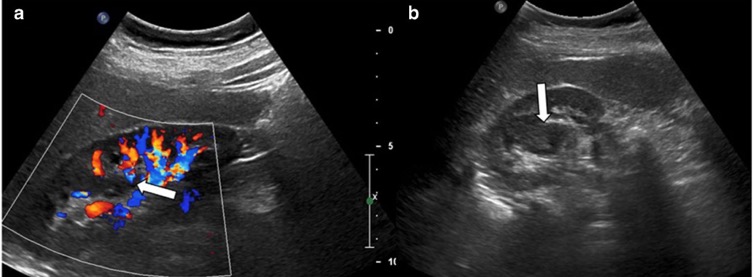

3. Pseudotumeurs rénales vasculaires

- Malformation artérioveineuse rénale